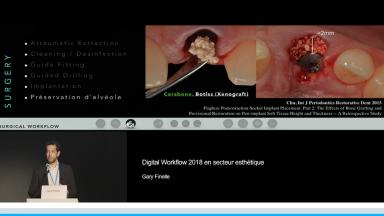

Au cours de cette présentation, le Dr Finelle nous montre tout l’intérêt du digital workflow dans une réhabilitation implantaire en secteur esthétique. Ainsi, à chaque étape de celle-ci, le numérique peut intervenir : au cours du diagnostic, de la chirurgie, de l’empreinte ou encore au cours de la réalisation prothétique.

Au travers de plusieurs cas cliniques, il nous est montré comment différents outils numériques permettent de préparer et d’obtenir une réhabilitation esthétique optimale. Au final, le digital workflow va apporter précision, prédictibilité, facilité de reproduction des formes dans la réhabilitation prothétique implantaire ; c’est également un formidable moyen de communication avec le patient.

- de décrire le workflow numérique du diagnostic à la prothèse définitive